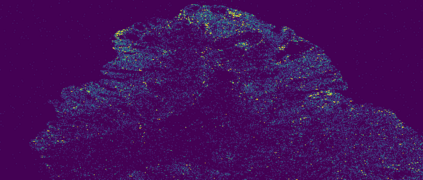

The usage of chemical imaging technologies is becoming a routine accompaniment to traditional methods in pathology. Significant technological advances have developed these next generation techniques to provide rich, spatially resolved, multidimensional chemical images. The rise of digital pathology has significantly enhanced the synergy of these imaging modalities with optical microscopy and immunohistochemistry, enhancing our understanding of the biological mechanisms and progression of diseases. Techniques such as imaging mass cytometry provide labelled multidimensional (multiplex) images of specific components used in conjunction with digital pathology techniques. These powerful techniques generate a wealth of high dimensional data that create significant challenges in data analysis. Unsupervised methods such as clustering are an attractive way to analyse these data, however, they require the selection of parameters such as the number of clusters. Here we propose a methodology to estimate the number of clusters in an automatic data-driven manner using a deep sparse autoencoder to embed the data into a lower dimensional space. We compute the density of regions in the embedded space, the majority of which are empty, enabling the high density regions to be detected as outliers and provide an estimate for the number of clusters. This framework provides a fully unsupervised and data-driven method to analyse multidimensional data. In this work we demonstrate our method using 45 multiplex imaging mass cytometry datasets. Moreover, our model is trained using only one of the datasets and the learned embedding is applied to the remaining 44 images providing an efficient process for data analysis. Finally, we demonstrate the high computational efficiency of our method which is two orders of magnitude faster than estimating via computing the sum squared distances as a function of cluster number.